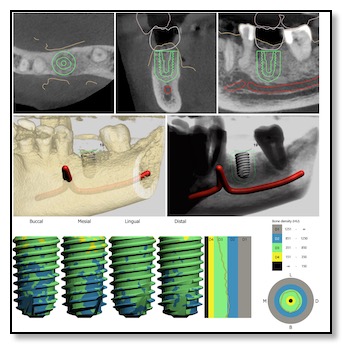

But thanks to recent advancements in digital dentistry, things have changed. Dr. Tsai is one of the few dentists in the Bay Area who has an in-house CT scanner (3D X-ray) and a 3D digital impressions camera.

She combines these technologies with a 3D printer. Here's how it works: she creates a digital model of your jawbone structure and overlays it with a 3D scan of your teeth and gums. Then, she aligns it with your natural bite to evaluate your biting and chewing patterns. This helps her determine the best position for the dental implant.

After this process, she collaborates with her lab to 3D print a template that acts as a guide for placing the implant with utmost precision regarding depth, angle, and location.

Designing this surgical guide is a meticulous process that usually takes about three weeks. It's especially crucial for all-ceramic dental implants, as well as standard ones.

Placement of Dental Implants and Bone Integration

Now that the surgical guide is ready, placing the implant in your jawbone is pretty quick. To make sure the surgery goes smoothly, Dr. Tsai might prescribe a round of antibiotics before placing the implant. The actual placement, along with a confirmatory CT scan to double-check its position, usually takes about an hour. Dr. Tsai will numb the area with local anesthesia, use the surgical guide to line things up perfectly, use different bone drills, and secure the implant in place. Depending on your situation, she might attach a healing cap right away or use a smaller cover screw for healing later on. It takes around four to five months for the implant to integrate with the surrounding bone, a process called bone integration or healing. The exact duration depends on things like your oral cavity chemistry, any medications you're taking, and your overall health.